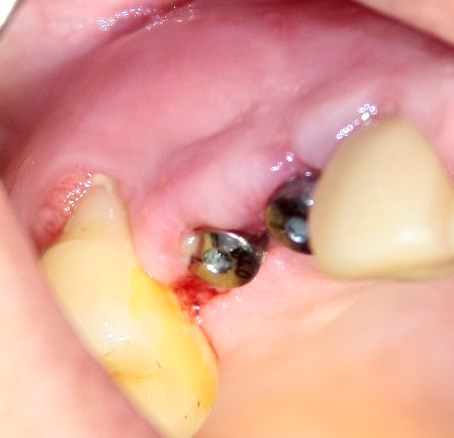

Опыт применения коллагеновой матрицы Mucograft в клинической практике.